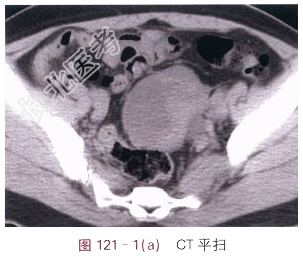

- [材料题] 患者,女,44岁,发现腹部包块2月余。体格检查:未见阳性体征。影像学资料如图121-1~图121-3所示。

- 简答题1、请叙述卵巢癌临床症状和该影像学表现?